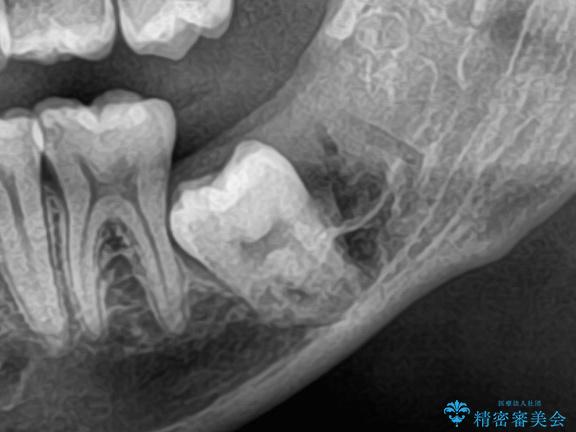

長期間の放置で骨が吸収した部位のインプラント治療

左下奥歯の抜歯後、長期間放置していたために、周囲の骨が吸収してしまいました。 特に垂直的な高さが不足しており、通常の術式ではインプラント埋入が難しい状態でした。